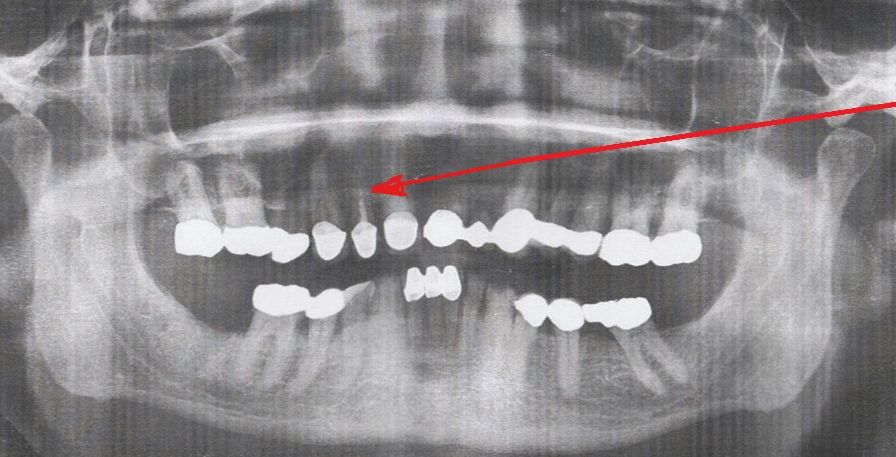

1 Implantat setzen mit Kronenversorgung

I. Befund des gesamten Gebisses / Behandlungsplan

Oberkiefer

11 k k 21

12 SKM x b 22

13 k k 23

14 )( k 24

15 k k 25

16 k k 26

17 k k 27

18 f f 28

Unterkiefer

48 f f 38

47 f k 37

46 k b 36

45 k k 35

44 k k 34

43 33

42 k 32

41 k k 31